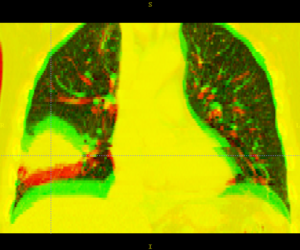

Thorax is a special case. Patient images are acquired using 4D-CT, and radiation treatment plan can be evaluated at each breathing phase. The volumes are aligned using deformable registration, and radiation dose from each phase is accumulated into a reference phase (e.g. exhale). This process is called "4D treatment planning."

Deformable registration of the phases within a 4D-CT is considered "easy". The reason for this is:

- Single-session imaging, so patient is already co-registered

- Single-session imaging, so no anatomic change

- High contrast of vessels against lung parenchema

However, the sliding of the lungs against the chest wall is difficult to model. We sometimes segment the images at the pleural boundary. This allows us to separate the moving set of organs from the non-moving set, which are registered separately. Ideally we would always do this, but segmentation is manual and therefore we usually skip this step.